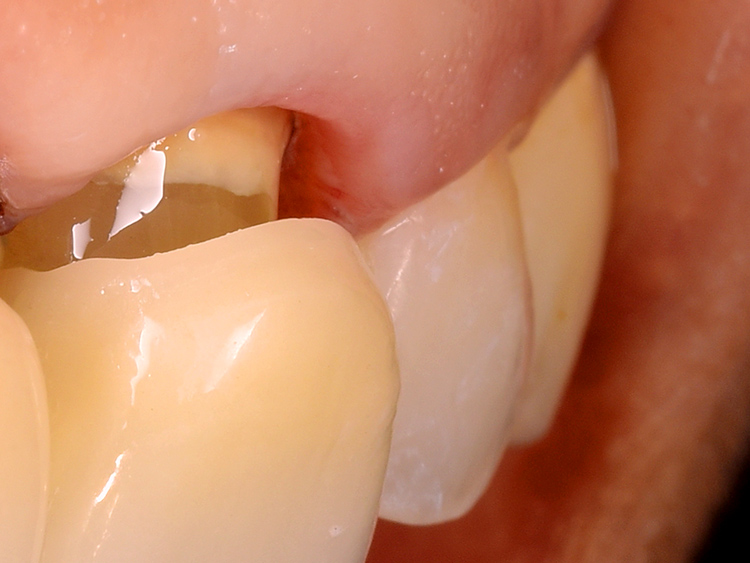

これ以上歯を傷めない低侵襲な歯質除去と形成

このような残存歯質が少ない症例では、これ以上のダメージを与えないよう細心の注意を払った治療が不可欠です。そのため、歯質を削る際には、通常用いられる高速回転ドリルではなく、特殊な超音波振動を用いた専用機器を採用します。これにより安全確実で優しく繊細な施術を可能にしています。